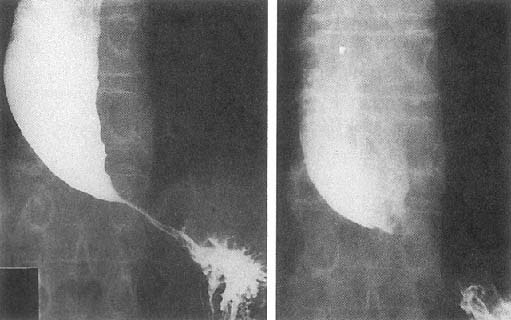

cancer need to be r/o